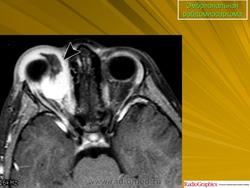

Рабдомиосаркома — чрезвычайно агрессивная опухоль орбиты, является наиболее частой причиной злокачественного роста в орбите у детей. Мальчики болеют почти в 2 раза чаще. Источником роста рабдомиосаркомы являются клетки скелетных мышц. Выделены три типа опухоли: эмбриональный, альвеолярный и плеоморфный, или дифференцированный. Последний тип встречается редко. У детей до 5 лет чаще развивается эмбриональный тип опухоли, после 5 лет — альвеолярный. Как правило, рабдомиосаркома состоит из элементов нескольких типов (смешанный вариант). Точный диагноз можно установить только на основании результатов электронной микроскопии.

Излюбленная локализация опухоли — верхневнутренний квадрант орбиты, поэтому в процесс рано вовлекаются мышца, поднимающая верхнее веко, и верхняя прямая мышца. Птоз, ограничение движений глаза, смещение его книзу и книзу кнутри — это первые признаки, на которые обращают внимание как сами больные, так и окружающие лица. У детей экзофтальм или смещение глаза при локализации опухоли в переднем отделе орбиты развивается в течение нескольких недель (рис. 20.23, а). У взрослых опухоль растет медленнее, в течение нескольких месяцев. Быстрое увеличение экзофтальма сопровождается появлением застойных изменений в эписклеральных венах, глазная щель полностью не смыкается, отмечаются инфильтраты на роговице и ее изъязвление. На глазном дне — застойный диск зрительного нерва. Первично развиваясь вблизи верхневнутренней стенки орбиты, опухоль быстро разрушает прилежащую тонкую костную стенку, прорастает в полость носа, вызывая носовые кровотечения. Ультразвуковое сканирование, компьютерная томография, термография и тонкоигольная аспирационная биопсия — это оптимальный диагностический комплекс инструментальных методов исследования при рабдомиосаркоме (рис. 20.23, б). Лечение комбинированное. Протокол лечения предусматривает предварительное проведение полихимиотерапии в течение 2 нед, после чего проводят наружное облучение орбиты. После комбинированного лечения более 3 лет живут 71 % больных.